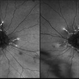

- Bilateral sclerosis of retinal vessles

- bilateral, retinal vessel

- Batchanaboina subba rao

- Optos widefield fundus camera

- Fundus photographs of an 71 -year-old women with bilateral sclerosed vessels s/p bilateral CRVO with PRP laser marks in the left eye. Known diabetic and hypertensive. Her visual acuity is good inspite of extensive sclerosis of vessles in both eyes - 20/30, N6 in the right eye and 20/80, N6 in the left eye.